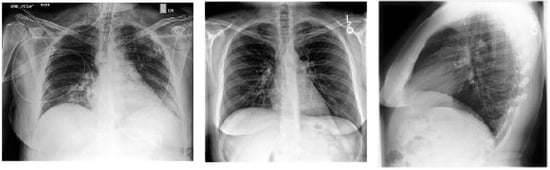

5.1.1. X-ray Imaging

5.3.1. AI-Powered Detection of COVID-19 from X-ray Images